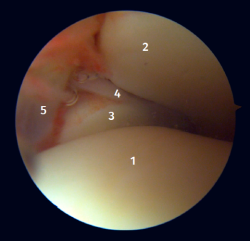

Arthroscopic anatomy of the medial complex

Arthroscopy allows us to see the deep fibers of the deltoid ligament, corresponding to the intra-articular portion of the ligament. Medial and proximal to the tip of the malleolus we have the insertion of the deep layer of the deltoid ligament. If there is no injury, we will see the anterior portion of the deep tibiotalar fibers. When injury is present, we can visualize the intermediate and posterior portion. The superficial bands, due to their more external location, are not visible by arthroscopy, unless there is no lesion of the deep bands (Figure 5).

Figure 5. A: anterior view of the medial recess of the ankle; B: the fibers of the deep tibiotalar ligament are tightened with the palpation probe.